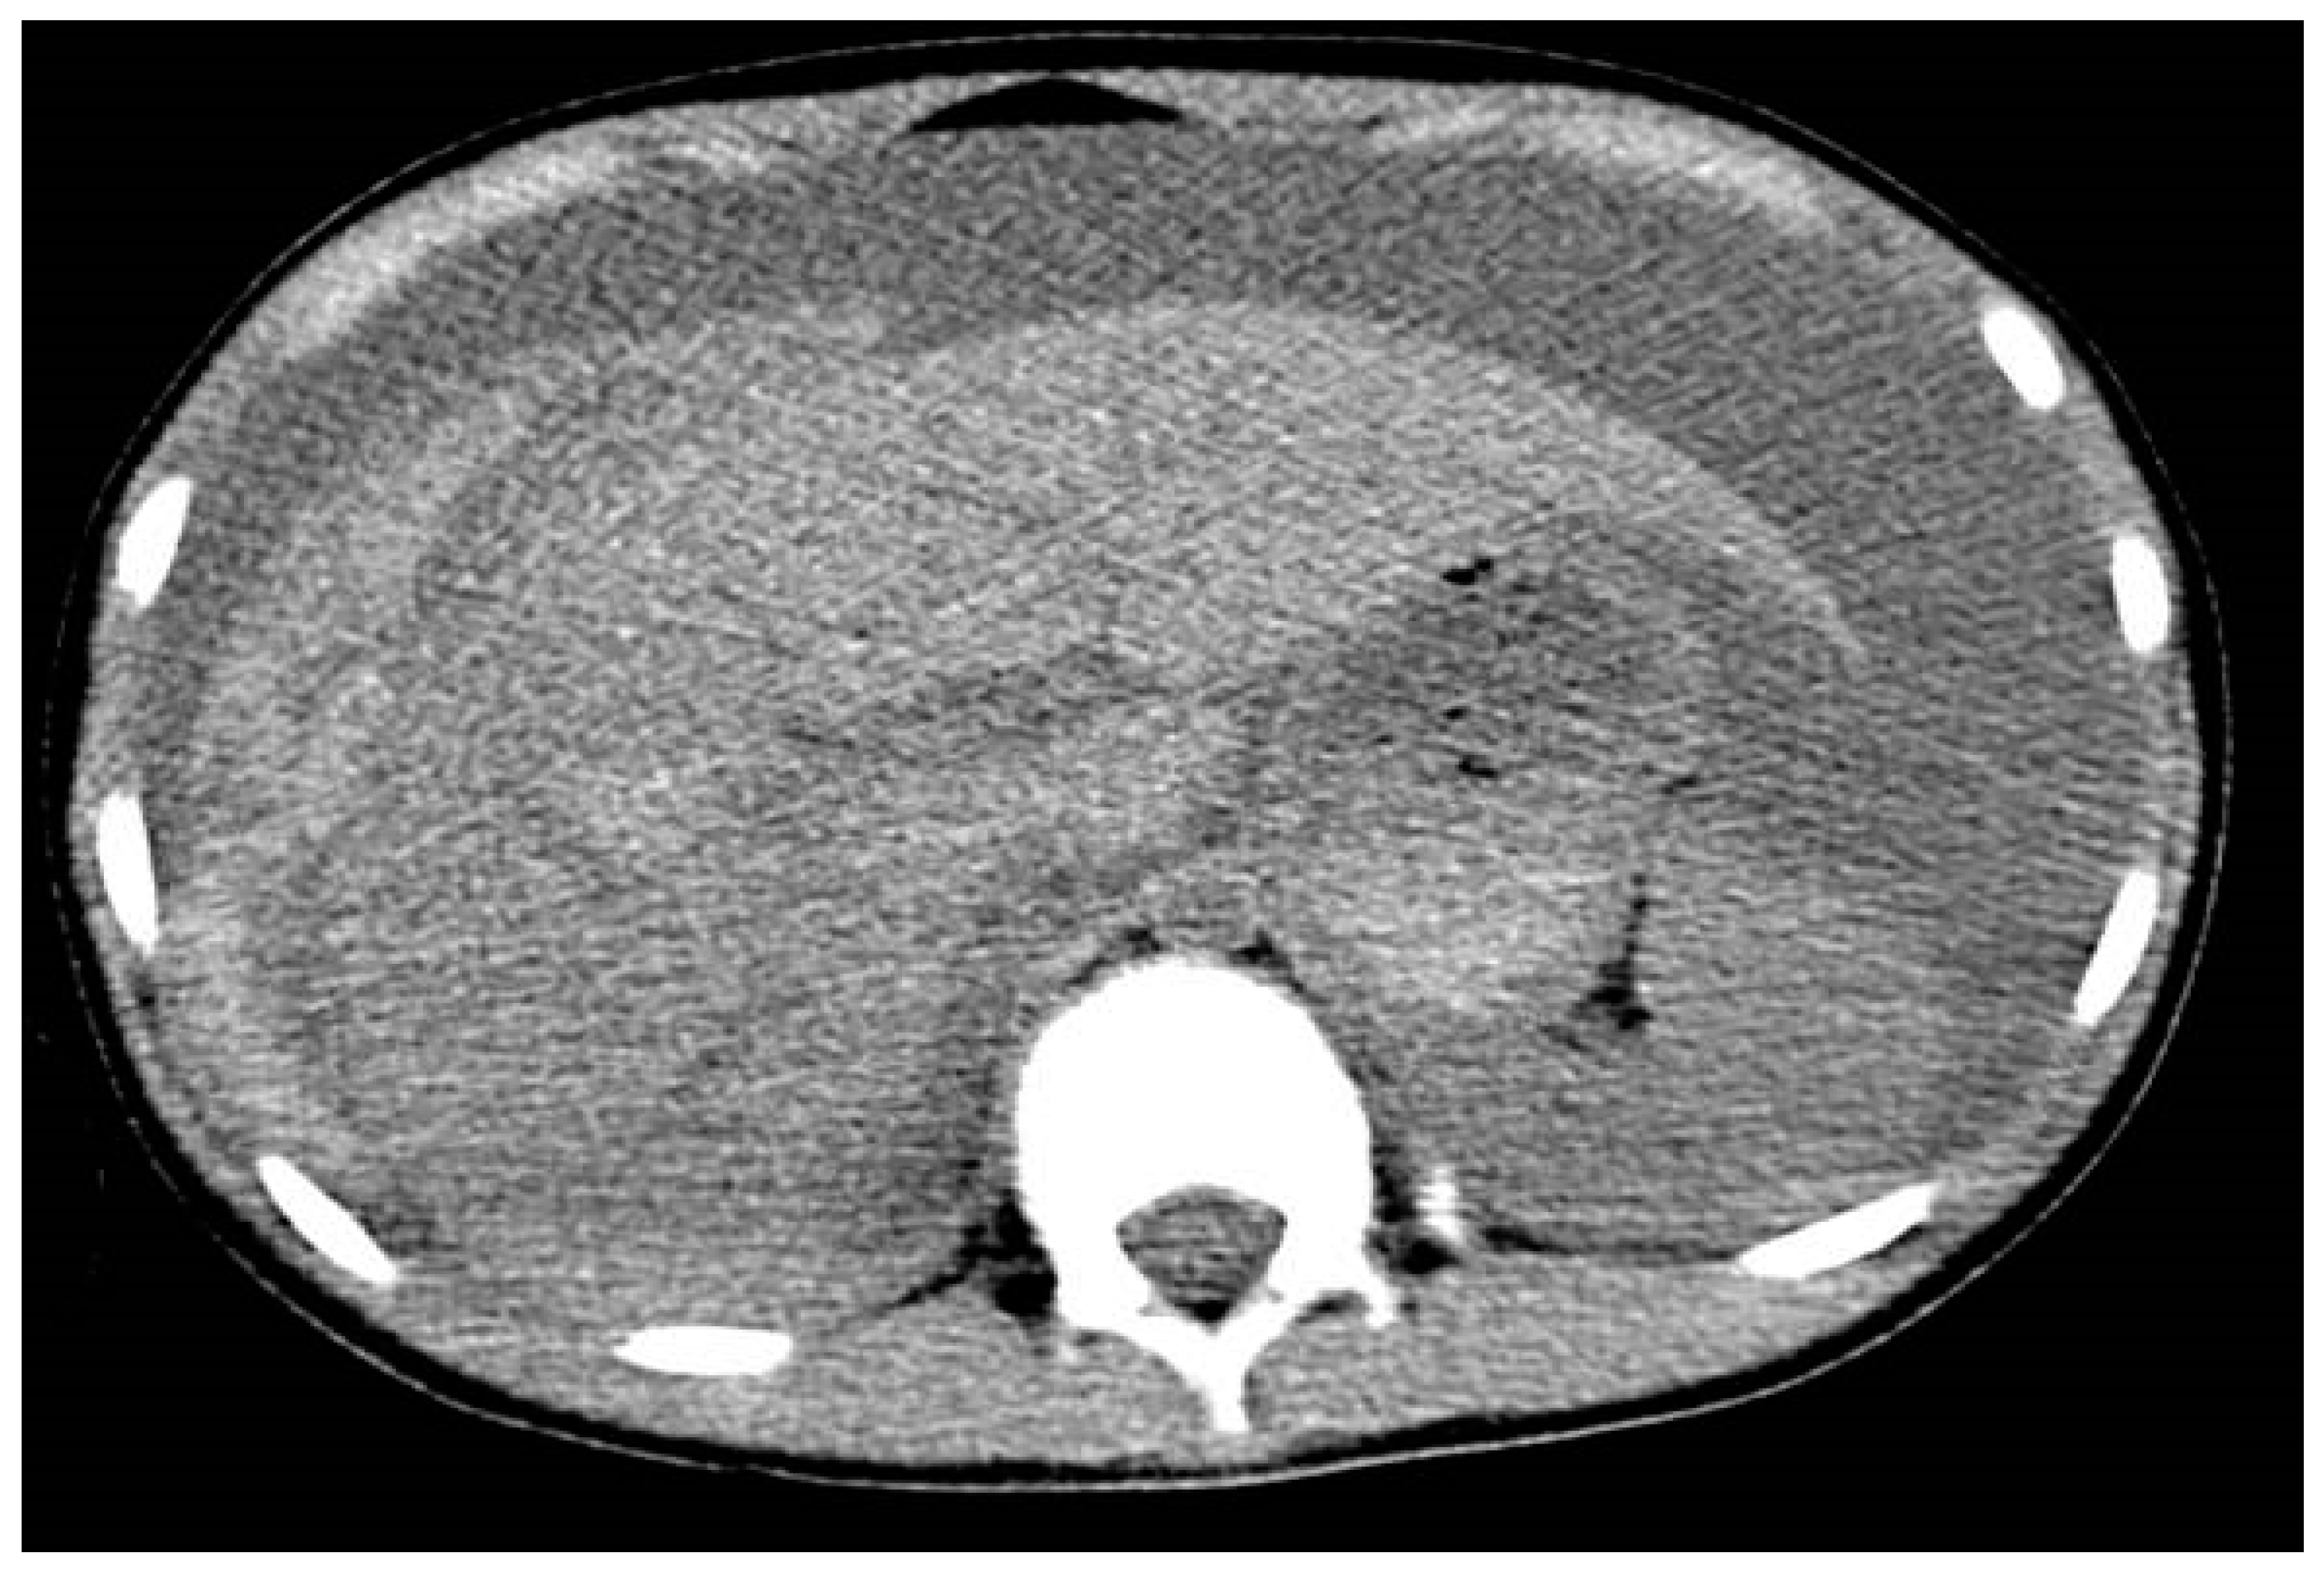

- Zakaria, O.M.; Daoud, M.Y.I.; Zakaria, H.M.; Al Naim, A.; Al Bshr, F.A.; Al Arfaj, H.; Al Abdulqader, A.A.; Al Mulhim, K.N.; Buhalim, M.A.; Al Moslem, A.R.; et al. Management of pediatric blunt abdominal trauma with split liver or spleen injuries: A retrospective study. Pediatr. Surg. Int. 2023, 39, 106. [Google Scholar] [CrossRef]